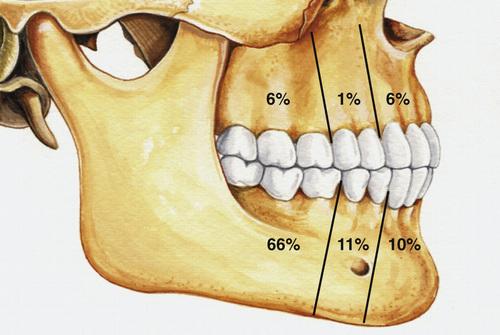

- most often involve mandibular third molars (65%)

- most often occurs in the mandible (60% to 80%)